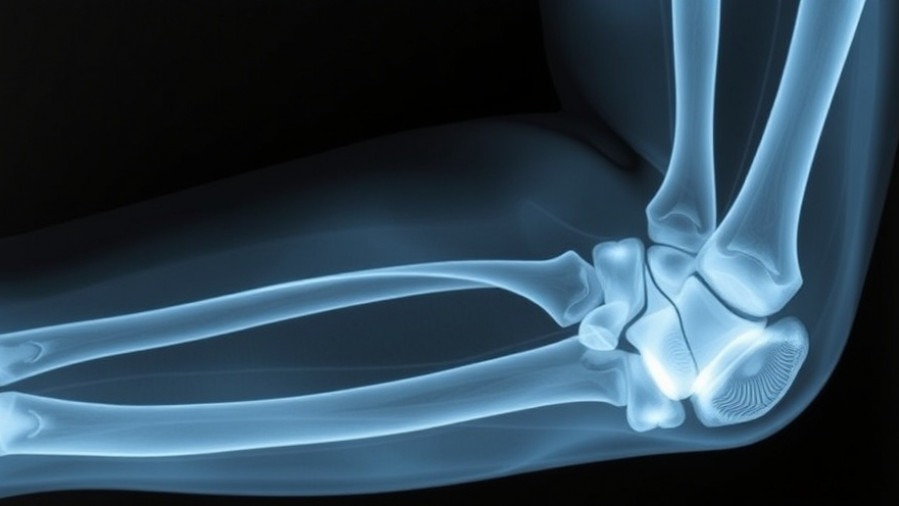

How Osteochondral Allograft Treatment Provides Hope for Young Athletes

Understanding Osteochondritis Dissecans

Osteochondritis dissecans is a progressive bone disease where a fragment of bone and cartilage becomes detached from the underlying bone, often due to inadequate blood supply. It is especially common among young, active individuals engaged in sports demanding repetitive elbow use. Symptoms typically include pain, swelling, and decreased range of motion, which can significantly impact an athlete's performance and quality of life.

The procedure involves replacing damaged bone and cartilage with fresh osteochondral grafts. The unique aspect of this approach is that it addresses both the bony and cartilage defects, providing a structural framework that promotes healing and restores normal elbow function. The evidence from Perkins' study suggests that patients not only achieve pain relief but also significant improvements in range of motion, having preoperative average flexion of 131.2° increasing to an average of 142.7° post-op.